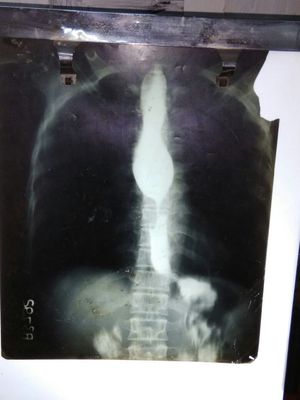

Wats the case of......achalsia cardia.... Esophagus constrictions